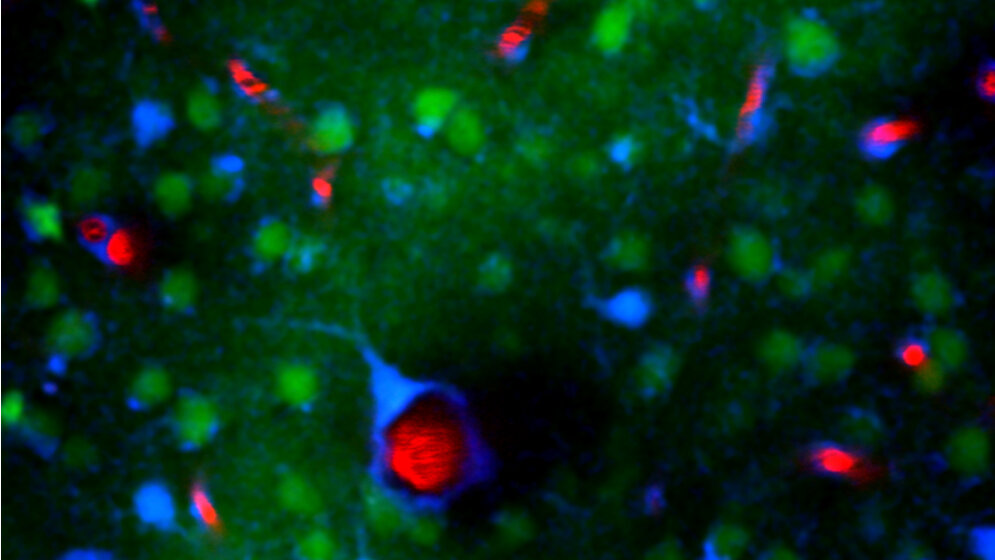

Die DZNE-Forscher fanden nun heraus, wie bei einer Depolarisationswelle verschiedene Geschehnisse und Zelltypen zusammenspielen und die Entladung verstärken. Eine entscheidende Rolle spielen dabei sogenannte Astrozyten. Diese Zellen sind gemeinsam mit den Nervenzellen des Gehirns zu einem Netzwerk verflochten und an diversen Stoffwechselprozessen beteiligt.

„Wenn die Nervenzellen depolarisieren, setzen sie große Mengen des Botenstoffs Glutamat frei. Das Glutamat diffundiert dann zu anderen Zellen, insbesondere zu benachbarten Astrozyten“, erläutert Petzold. „Das wusste man schon. Doch wir konnten nun zeigen, was im Anschluss passiert: Das Glutamat lässt die Konzentration an Kalzium innerhalb der Astrozyten in die Höhe schnellen. Infolgedessen setzen die Astrozyten ebenfalls Glutamat frei. Das kann dann wiederum auf Nervenzellen einwirken. So kommt ein Teufelskreis in Gang, der die Depolarisationswelle potenziert. Dabei wirken die Astrozyten als Verstärker.“